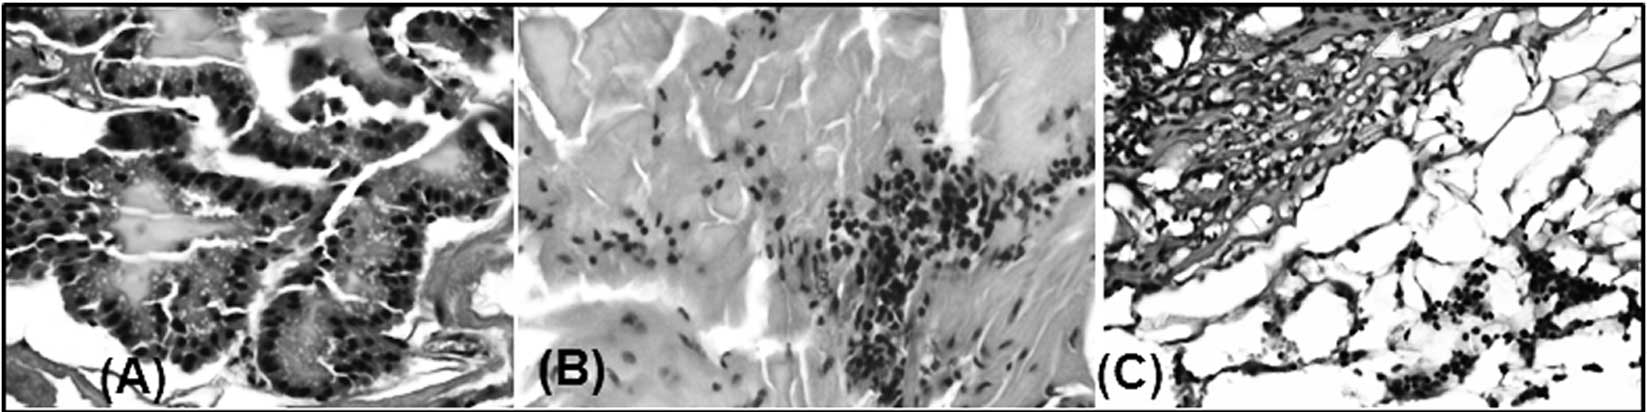

Degree of inflammation (infiltrating cells) in the prostates of PSA-Tg mice

Prostate tissue samples from different age groups of PSA-Tg mice were further analyzed for the intensity of inflammation (analyzed by quantifying infiltrating cells in the tissue). Analysis of H&E-stained slides showed that there was no infiltration of inflammatory cells in the prostate tissue samples harvested from the youngest mice (Fig. 2A). However, we found an increase in the intensity of inflammation in the samples harvested from 15-month-old mice (Fig. 2B). Furthermore, we noted a significant difference in the glandular architecture between samples from the different age groups. The prostates of the younger animals were healthy with normal-appearing glands that were organized in an orderly manner with no evidence of inflammation (Fig. 2A). By contrast, progressive degenerative glandular changes as well as an increase in inflammation were observed in the older mice, with the worst changes being detected in the oldest mice. Degeneration of epithelial lining and intraluminal sloughing of epithelial cells was extremely high along with a significant depletion of the prostatic secretion in the prostates of elderly PSA-Tg mice (Fig. 2C). Overall, the prostate tissue from 24-month-old elderly mice was severely damaged, possibly due to chronic inflammation; however, the examined slides did not reveal any sign of neoplasm. Thus, the presence of inflammation corresponds with the mRNA expression of the MIC-1 gene in the prostate tissues harvested from the PSA-Tg mice, confirming the hypothesis that an increase in the expression level of MIC-1 with increasing age may be due to inflammatory response. It has been reported that inflammation and aging influence the expression level of MIC-1 in correlation with infiltration of macrophages in the rat prostate (21).

Figure 2

Representation of H&E-stained slides of the formalin-fixed, paraffin-embedded prostate tissues from prostate-specific antigen-transgenic mice of different ages. (A) Representative example of normal prostate tissue harvested from a 4-week-old mouse with no evidence of inflammation. (B) and (C) Representative photomicrographs of prostate sections from a 15- and 24-month-old mouse, respectively, at different magnifications. An aggregate of chronic inflammatory cells is noted in (B), and in (C) diffuse chronic inflammation in the stroma (right upper corner) and glandular degeneration.